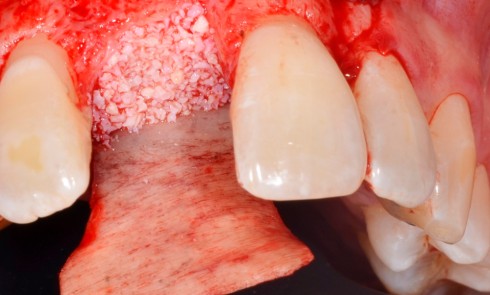

Article réservé à nos abonnés Réhabilitations maxillaires complètes de grande étendue

À travers deux cas cliniques, cet article va se focaliser sur les réhabilitations complètes fixes implanto-portées et distinguer : –...